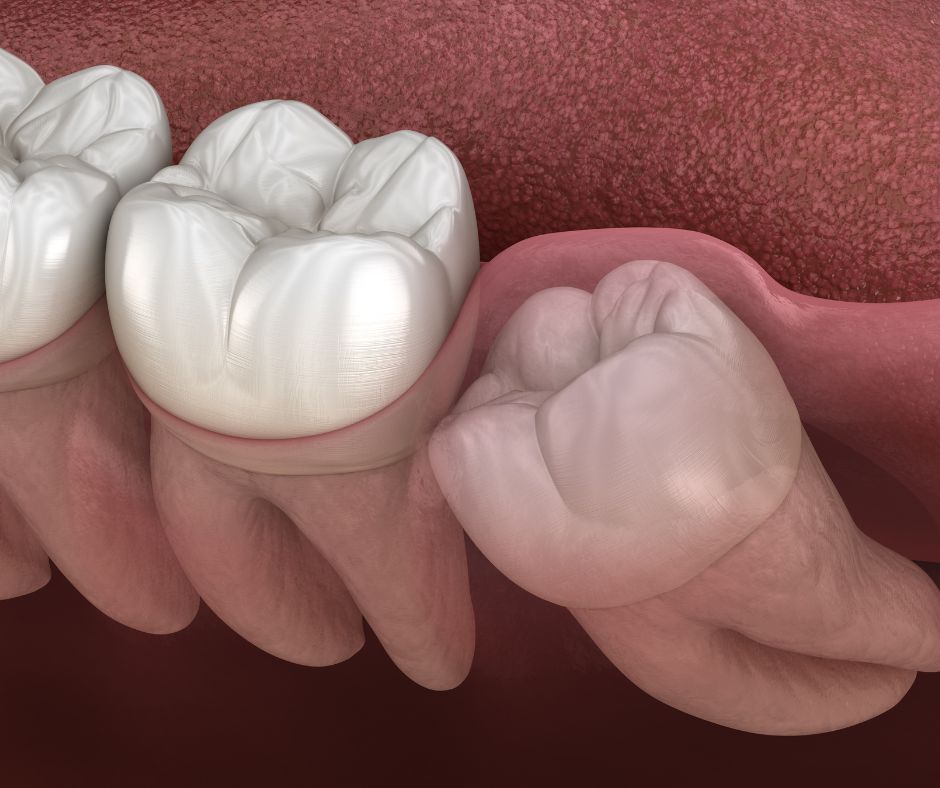

WISDOM TOOTH EXTRACTION

Wisdom teeth are the last molars to develop, usually emerging in the late teens or early twenties. In many cases, there is not enough space in the jaw for them to grow properly, which can lead to pain, swelling, infection, or damage to nearby teeth.

WHEN IS WISDOM TOOTH EXTRACTION NECESSARY?

- Impacted or partially erupted wisdom teeth.

- Damage to adjacent teeth.